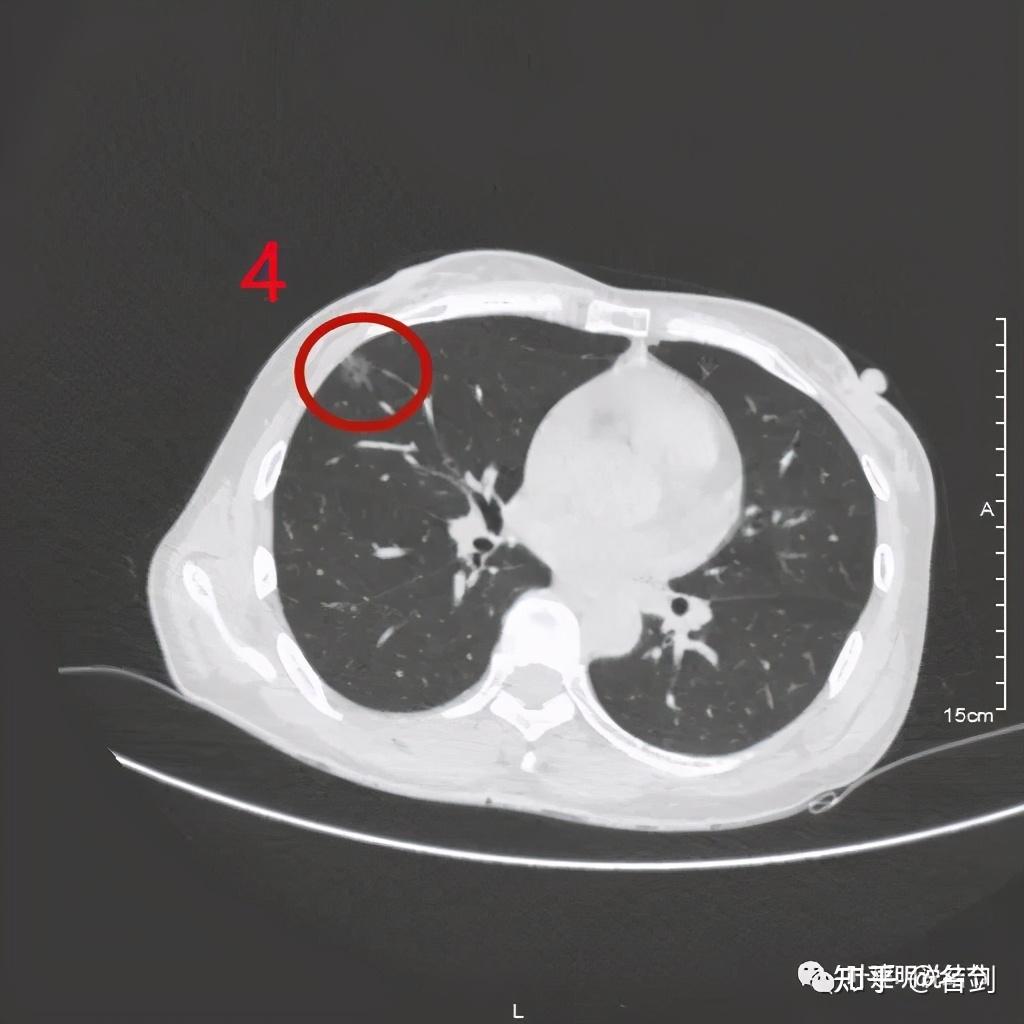

肺结节伴胸膜牵拉,毛刺是癌吗?肿瘤科医生患肺结节也焦虑

结节很小,直径6mm,但已经牵拉胸膜,需要密切随访了.